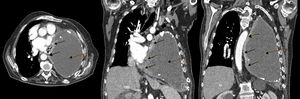

In view of the patient's poor progress after evacuation of pleural fluid and findings suggestive of right heart failure, transthoracic echocardiography was performed, which revealed a hypoechogenic mass in the inferolateral wall of the left ventricle, with dilation of the left atrium, slight pericardial effusion, preserved LVEF, and dilated inferior vena cava without inspiratory collapse. Chest–abdomen computed tomography (CT) was performed, showing a soft tissue mass in the medial portion of the posterior chest wall, measuring 6×3cm, with pericardial infiltration, mass effect, and associated small pericardial effusion. A significant increase in the pleural collection compared to previous studies was visualized, occupying practically the entire hemithorax, causing compressive atelectasis of the lung with contralateral mediastinal shift and cardiac compression (Fig. 1).

Chest CT with contrast medium, axial (left) and coronal slices (center and right): pleural mass in the medial portion of the anterior left chest wall with pericardial infiltration (solid arrows), and a large collection in the left hemithorax, corresponding with chronic pyothorax (dotted arrows), together causing contralateral mediastinal shift and cardiac compression.